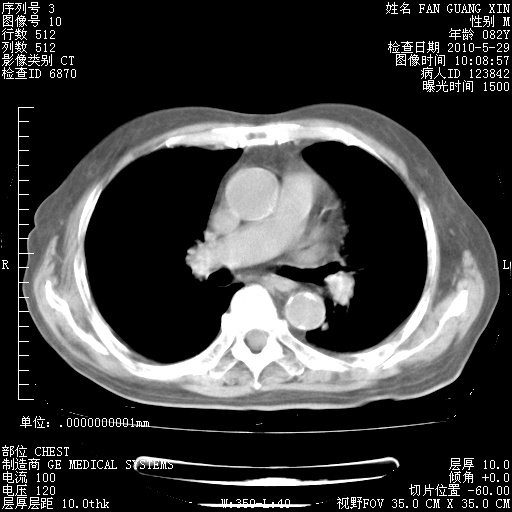

再治疗10天后的肺部CT 纵膈窗